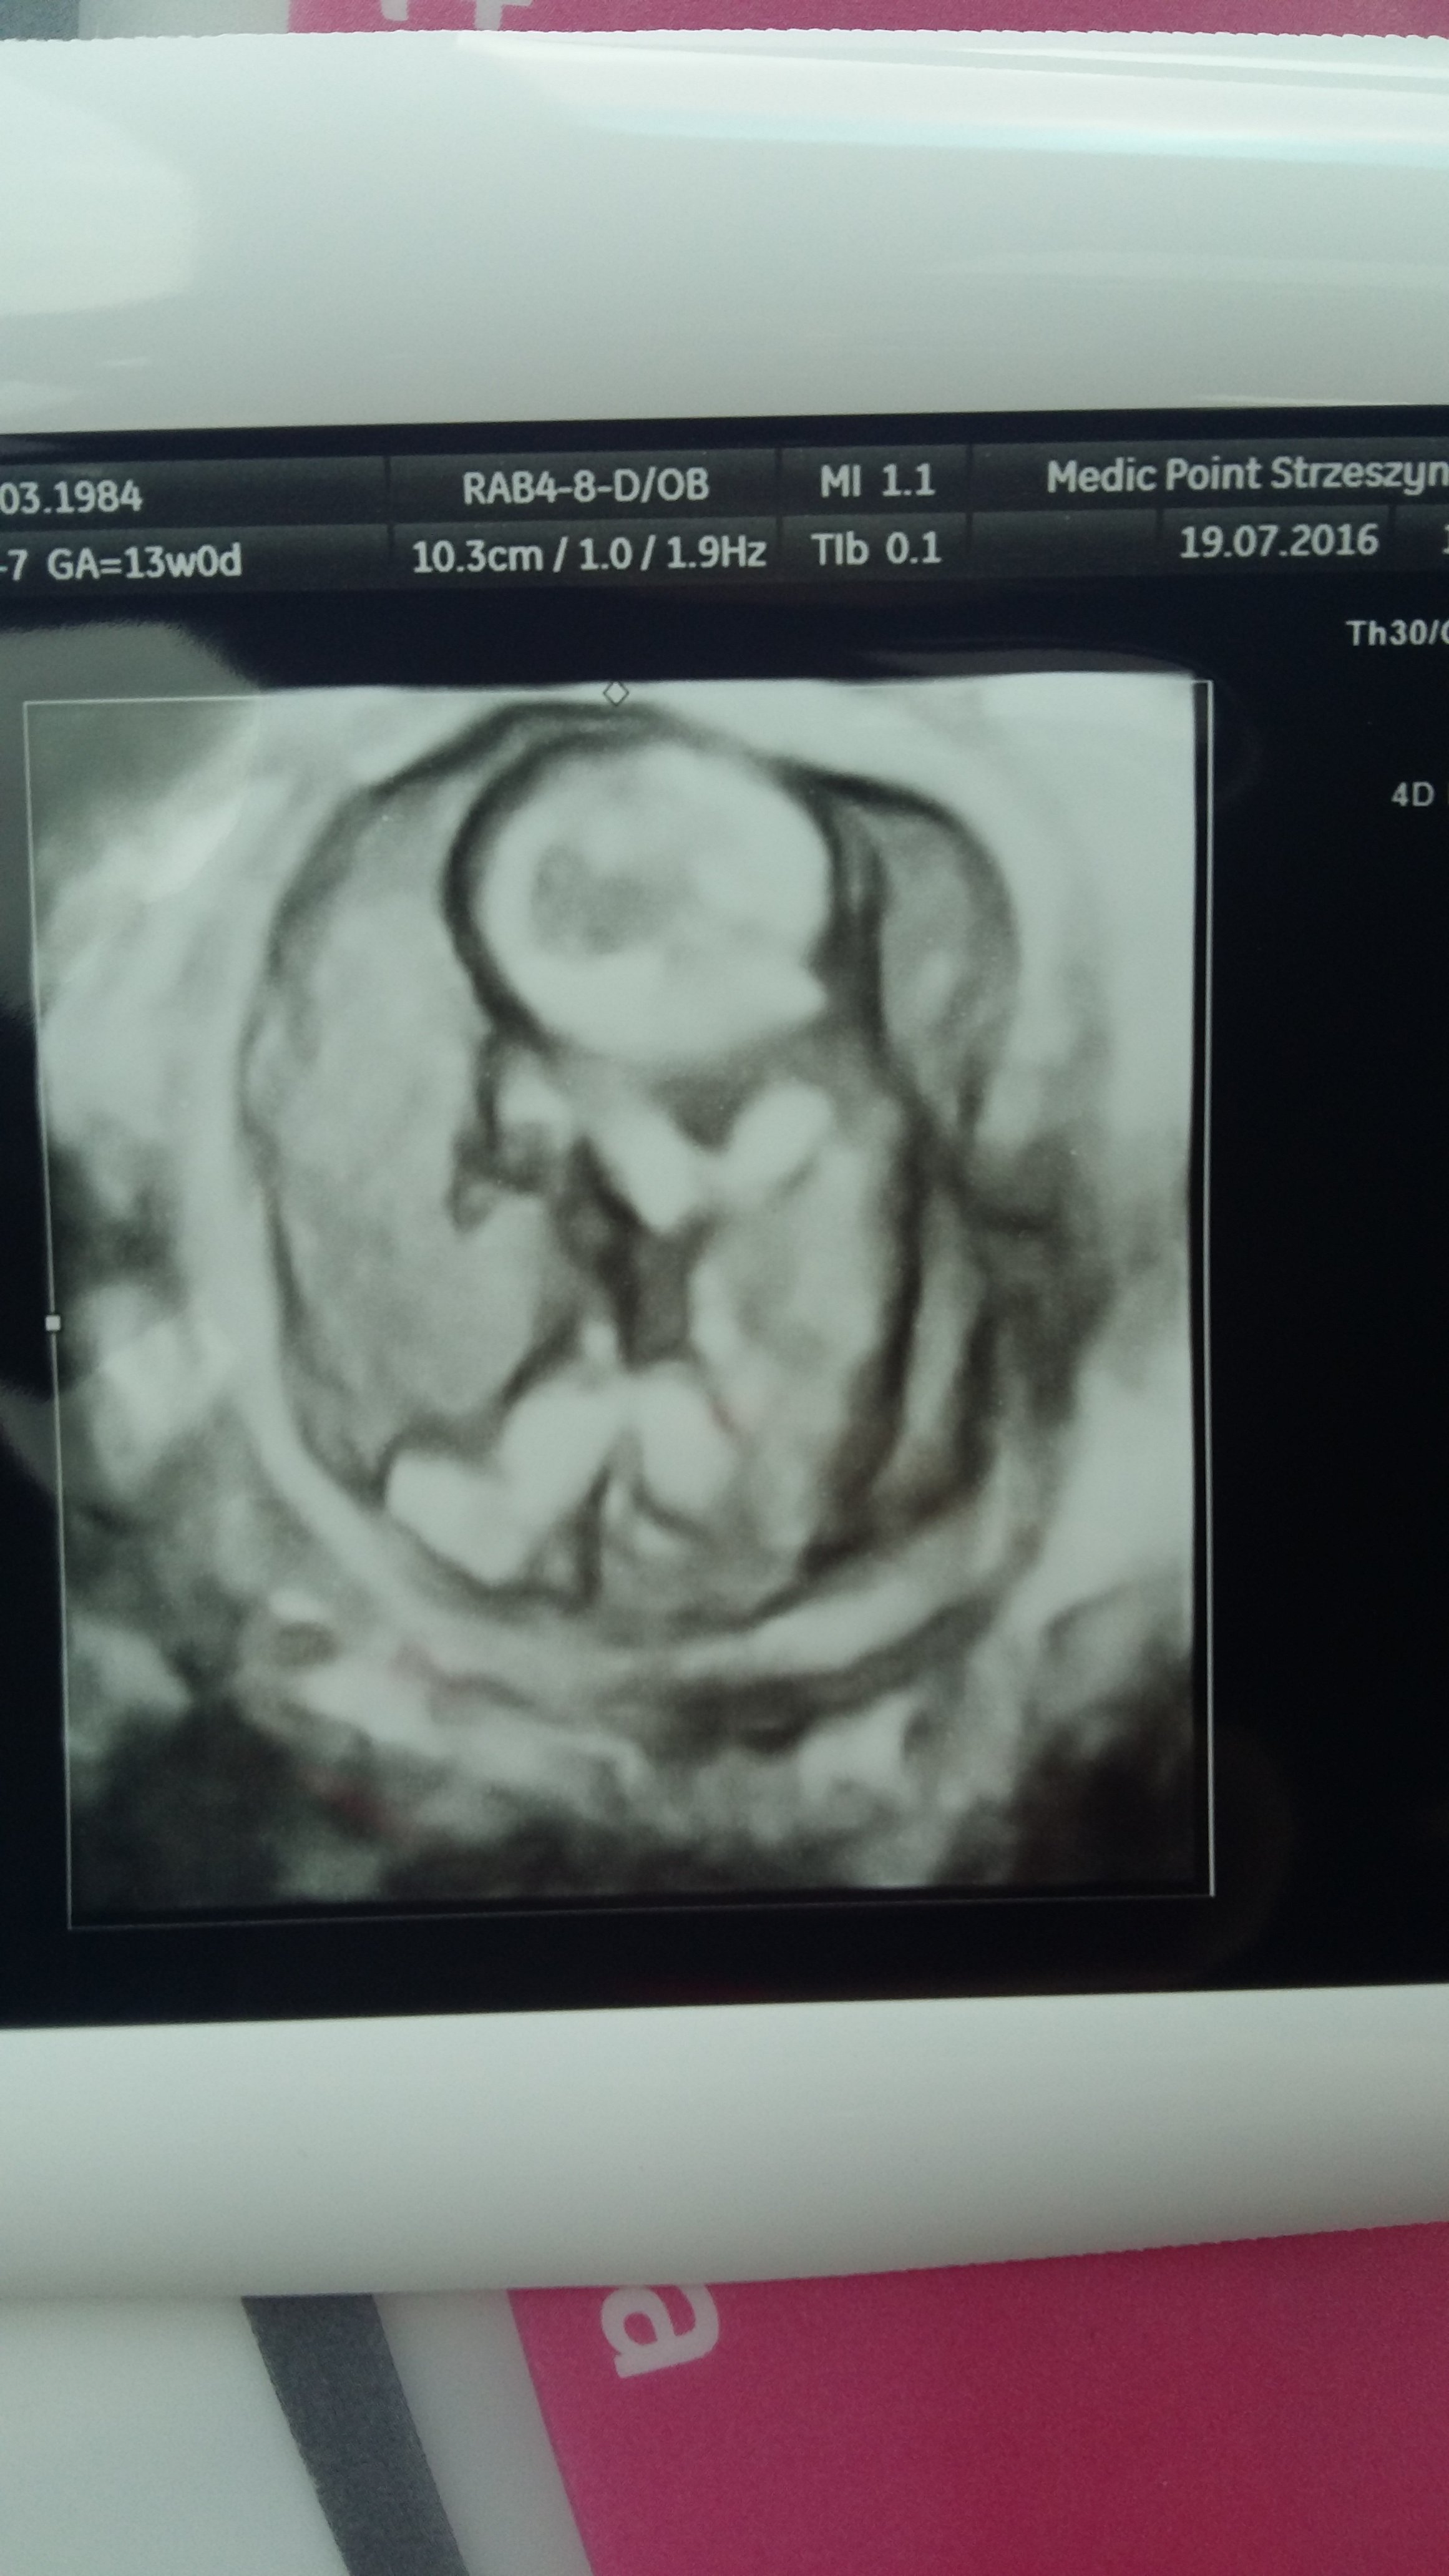

a oto moje malenstwo, dzis niechcialo pokazac co ma miedzy nozkamiginka mowila ze kolejnej juz sie upewnimy kto tam mieszka

pierwsze usg z piatku, a te w 3d z dzis